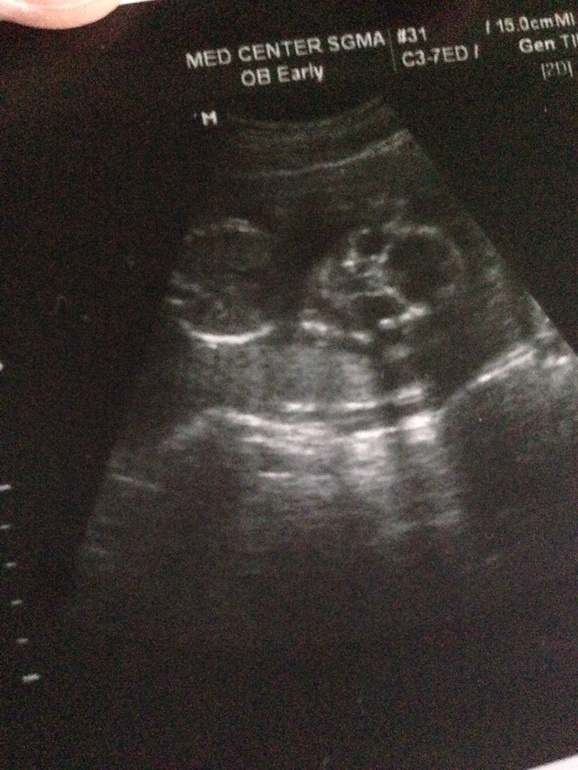

Вот и 2ой скриннинг мы прошли успешно))+фото подкат

УЗИ, КТГ, доплерДечоночки привет . У нас сегодня был очень важный день,который я ждала с нетерпением)) малыш так ковырялся, когда мы сидели ожидали свое время) Честно говоря, куда бы я не собиралась всегда и везде опаздываю . Но скриннинг пришла на 30 минут раньше . |

. На УЗИ 15 недель масик так активничал, что его было нереально рассмотреть, а тут такой важненький, спокойный лежал, конечно, мамка перед УЗИ хорошо натрескалась вкусностей, вот и лежал балдел

. Маленький наш лежал себе там пальчик сосал, такой маленький, такой сладенький

. все показатели в норме, все органы развиваются как положено, по сроку. ВООБЩЕМ Я САМАЯ СЧАСТЛИВАЯ МАМОЧКА))